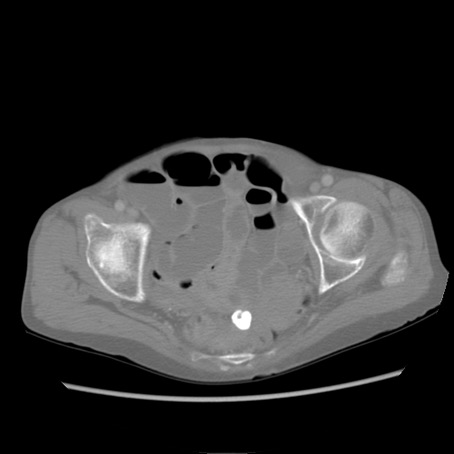

症例25(横断像)

【症例】80歳代女性

【主訴】胸のつかえ感

【現病歴】約9時間前に食後から胸のつかえた感じあり、嘔吐あり、来院。

【既往歴】胃癌(全摘)、胆摘、虫垂炎

【身体所見】心窩部に圧痛あり、反跳痛なし。

【データ】WBC 5700、CRP 0.05